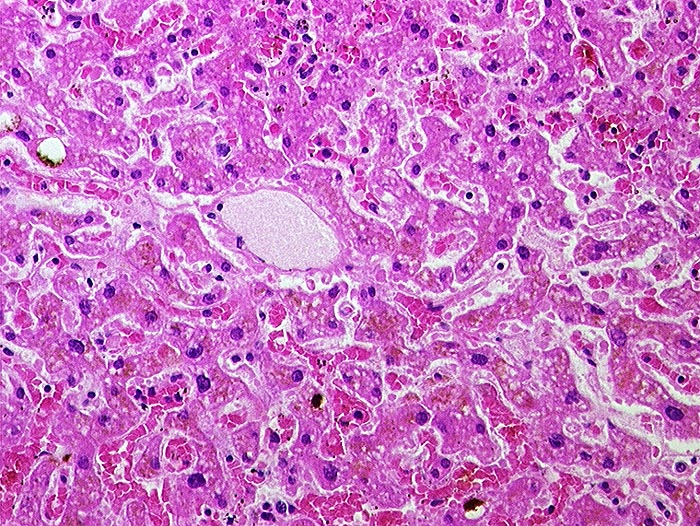

Subakute Stauung

vaskulär / Durchblutungsstörung

Leber

In der Mitte eine Zentralvene. Die angrenzenden Sinusoide sind deutlich erweitert und prall gefüllt mit Erythrozyten. Die Leberzellbalken sind leicht verschmälert (Druckatrophie). Die perivenösen Hepatozyten enthalten teilweise braunes Lipofuscinpigment.

In der Bindegewebsfärbung kein vermehrter Fasernachweis rund um die Zentralvene.